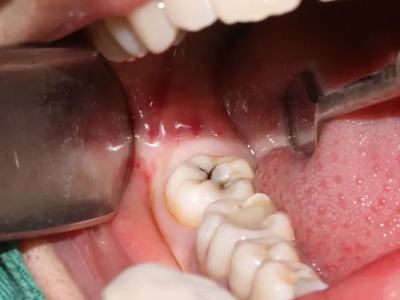

阻生牙是指由于邻牙、骨或软组织的阻碍而只能部分萌出或完全不能萌出,且以后也不能萌出的牙。引起牙阻生的成因,主要是由于颌骨缺乏足够的空间容纳全部恒牙。常见的阻生牙为下颌第三磨牙、上颌第三磨牙及上颌尖牙。

阻生牙可反复引起冠周炎,或引起邻牙牙根吸收和破坏,位置不正,不能完全萌出,好发部位是上、下颌第三磨牙。

对于阻生牙的处置需要首先明确阻生牙齿发育情况是否正常,对于由于早期外伤或其他原因造成发育异常,如牙根弯曲、短根等情况的阻生牙,还应根据患者的综合情况,决定牙齿是否保留。